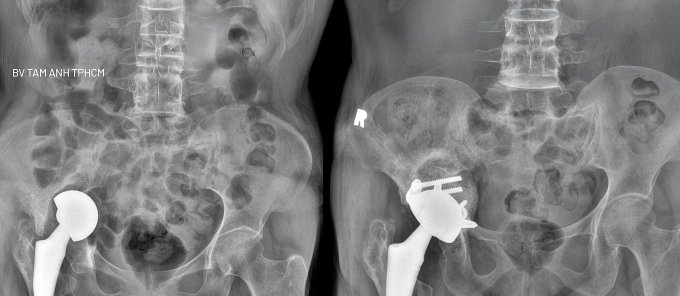

Kết quả chụp X-quang và CT tại Bệnh viện Đa khoa Tâm Anh TP HCM cho thấy khớp háng phải của người bệnh đã di lệch khỏi vị trí ban đầu, đi sâu vào trong khung chậu, làm chân phải ngắn hơn bên trái 4 cm. Ổ cối tiêu xương gần như hoàn toàn, không còn xương để chịu lực khi người bệnh cử động. Tình trạng này gây đau nhiều và đi lại khó khăn, dẫn đến teo cơ vùng háng. ThS.BS.CKI Nguyễn Văn Lưu, Trưởng đơn vị Phẫu thuật trong ngày, cho biết người bệnh phải phẫu thuật thay lại khớp háng để giải quyết đau và khôi phục khả năng vận động.

Bác sĩ sử dụng phần mềm TraumaCad để tính toán và tìm ra loại khớp phù hợp nhất với bà Nga, đảm bảo khả năng đi lại và cảm giác tự nhiên sau mổ. Người bệnh được ghép xương để khôi phục lại hình dáng ổ cối và thay khớp háng nhân tạo có thiết kế đặc biệt. Ổ cối mới có vít và đai móc bên ngoài giúp chuyển lực từ ổ cối lên xung quanh rìa xương chậu, tăng cường khả năng chịu lực cho khớp háng sau mổ và ngăn ngừa nguy cơ di lệch. Với chuôi xương đùi, bác sĩ sử dụng loại chuôi dài, có kích thước vừa khít với lòng tủy xương, thêm xi măng để giữ vững tối đa, hạn chế các biến chứng cơ học.

Ngày đầu sau mổ, bà Nga giảm đau đáng kể, hai chân cân bằng, có thể tập đi lại với khung, tập phục hồi chức năng để kéo giãn phần cơ mông đùi đã bị teo sau thời gian dài hạn chế đi lại. Bác sĩ Lưu tiên lượng sau khoảng 6-12 tuần, khi phần xương ghép đã lành và kết nối vững chắc với nhau tạo thành ổ cối mới, người bệnh có thể chịu lực tối đa và đi lại như bình thường.